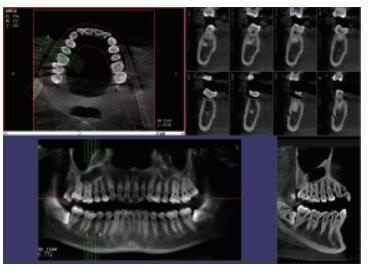

三维重建任意断层

专有三维重建算法,可提供任意位置高清断层影像。

高清口腔全景影像

通过三维容积影像,提取高清口腔全景影像。

多平面组合重建

可同时观察轴向面、冠状面和矢状面图像,方便临床诊断。